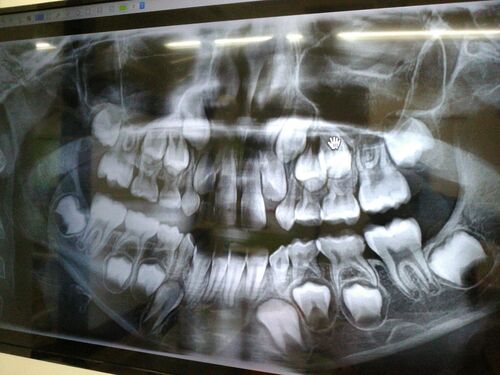

昨日はキキの歯医者の日だった。悩みに悩んだ末、ようやく矯正を始める覚悟ができた。(矯正するのは私じゃないけど!笑) キキの覚悟ができたかどうかは、定かではない。(定かじゃないんかい!笑)どちらかと言えば、私が矯正のための40万を払う覚悟ができ…